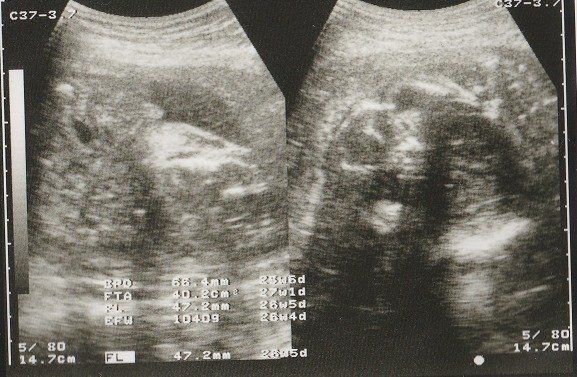

妊娠26週目のエコー写真 男の子であることが判明

左側のエコー画像に、男の子のシンボルが写っています。人によっては、生まれるまで男の子か女の子か告げて欲しくないという方もいらっしゃるようですが、私の場合、お医者さんに何も聞かれずに「男の子ですね」と言われました。

左側は頭の画像。赤ちゃんの頭もだいぶ大きくなりました。